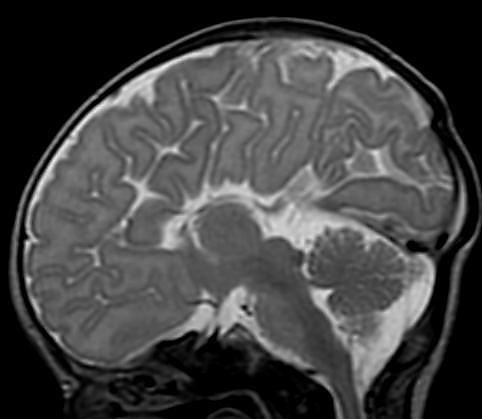

Differential for “cyst in the posterior fossa” starts with whether the vermis is normal or not.

Is the vermis normal? Can you identify the normal structures of the Vermis?

Malrotated hypoplastic vermis, with vertical primary fissure.

“OPEN” fastigial point of the fourth ventricle. Hypoplastic cerebellar hemispheres.

Enlarged posterior fossa

Cystic dilatation 4th ventricle

Uplifted tentorium, TSV sinus, torcula

“torcula-lambdoid inversion” with torcula above the lambdoid suture

Agenetic or hypogenetic vermis with “vermian tail, pushed upward

Cerebellar hypoplasia

CC anomalies 32%

Hydrocephalus up to 90%

Aqueductal stenosis

4th ventricle outlet obstruction

Polymicrogyria, heteropia 5-10%

Occipital Meningo-Encephaloceles 16%

Syndromic = Extracranial anomalies 50%